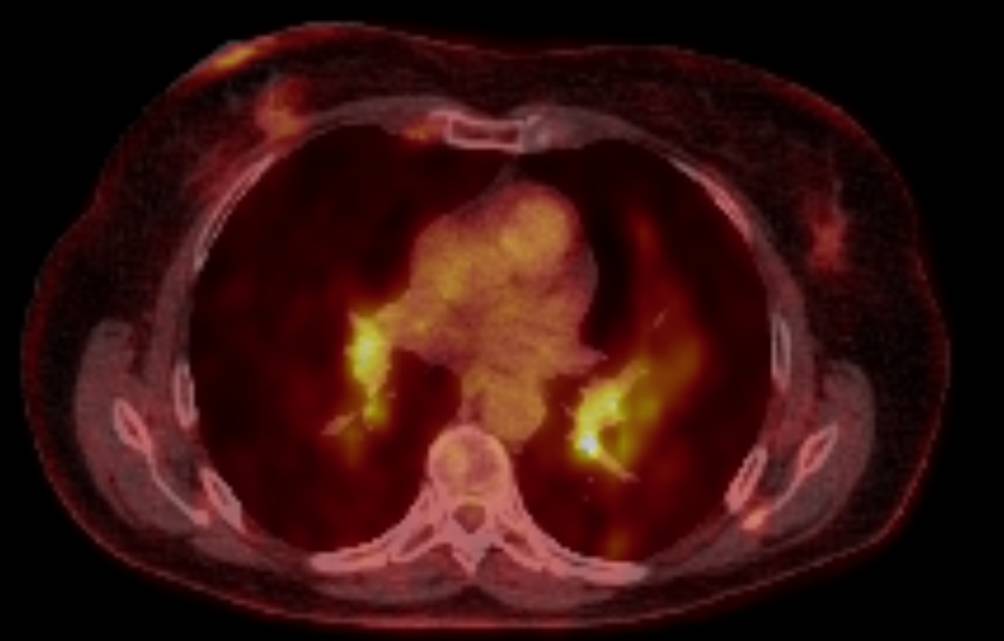

Im Rahmen einer 68 Ga-DOTANOC-PET/CT-Verlaufskontrolle zeigten sich zwei Jahre später neben den bereits bekannten Somatostatinrezeptor-positiven Leberherden in Bezug auf Größe und Anzahl auch erstmalig neu aufgetretene Lymphknoten mit pathologischer Traceraktivität, einerseits im Kopf‑/Halsbereich, andererseits jedoch auch retroklavikulär und axillär sowie inguinal (Abb. 1 und 2).

Abb. 1

68Ga-DOTANOC-PET/CT: Lymphknoten mit vermehrter Somatostatinrezeptor-Expression beidseits axillär bzw. zervikal